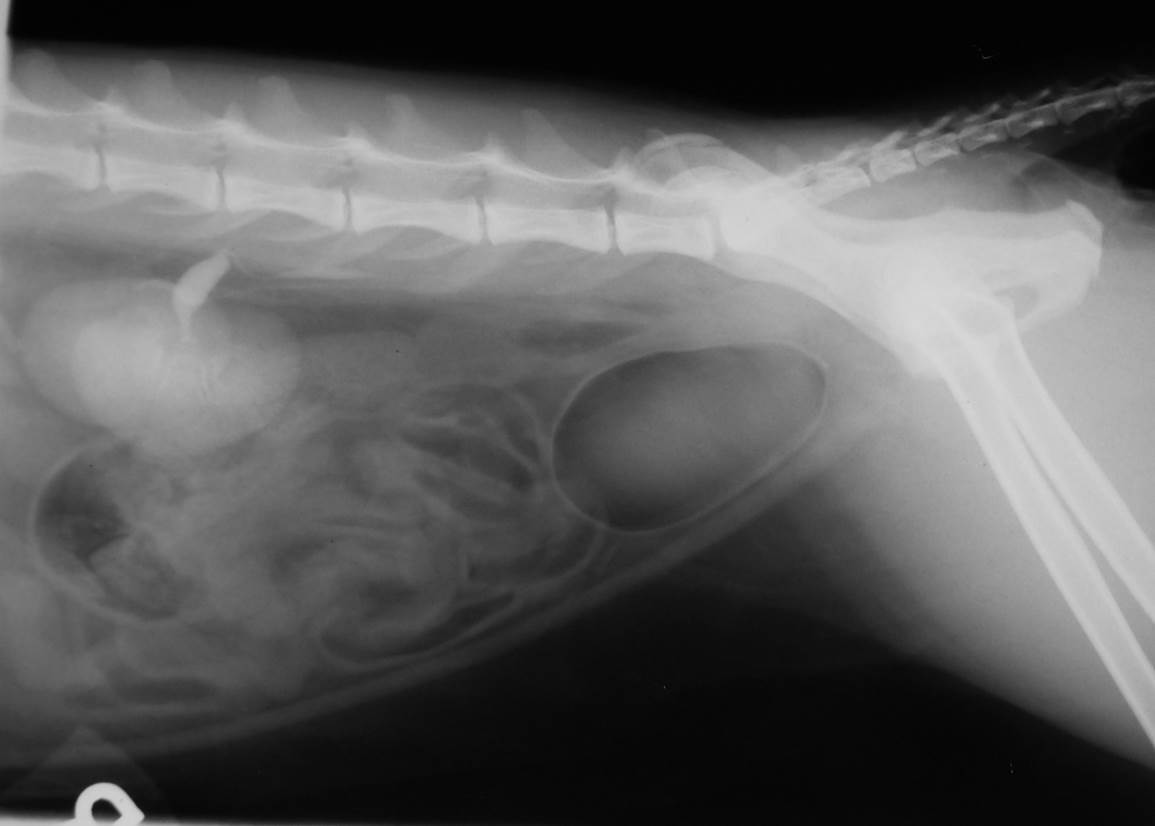

Case Nutty

Discuss this case?

–loss of the normal tear drop shape of the bladder

–urethra relatively short/kinked

–urinalysis including culture

–treatment trial with phenylpropanolamine +/- estriol